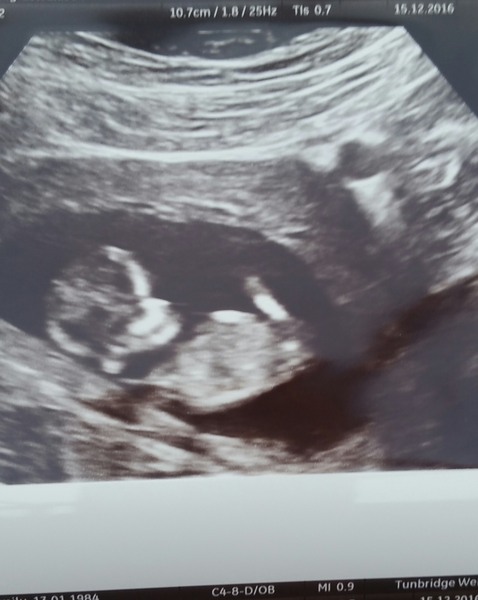

mummycaitlin · 14/12/2016 21:24

Scan photo

We had our private scan this afternoon, all is fine and everything progressing as it should do. They've moved my date to 9 weeks exactly with EDD of 19/07. We got to see the baby jigging away and it moved its little T Rex 'arm buds'. Excited for my next scan on the 29th. Ow as will see more shape to the baby.